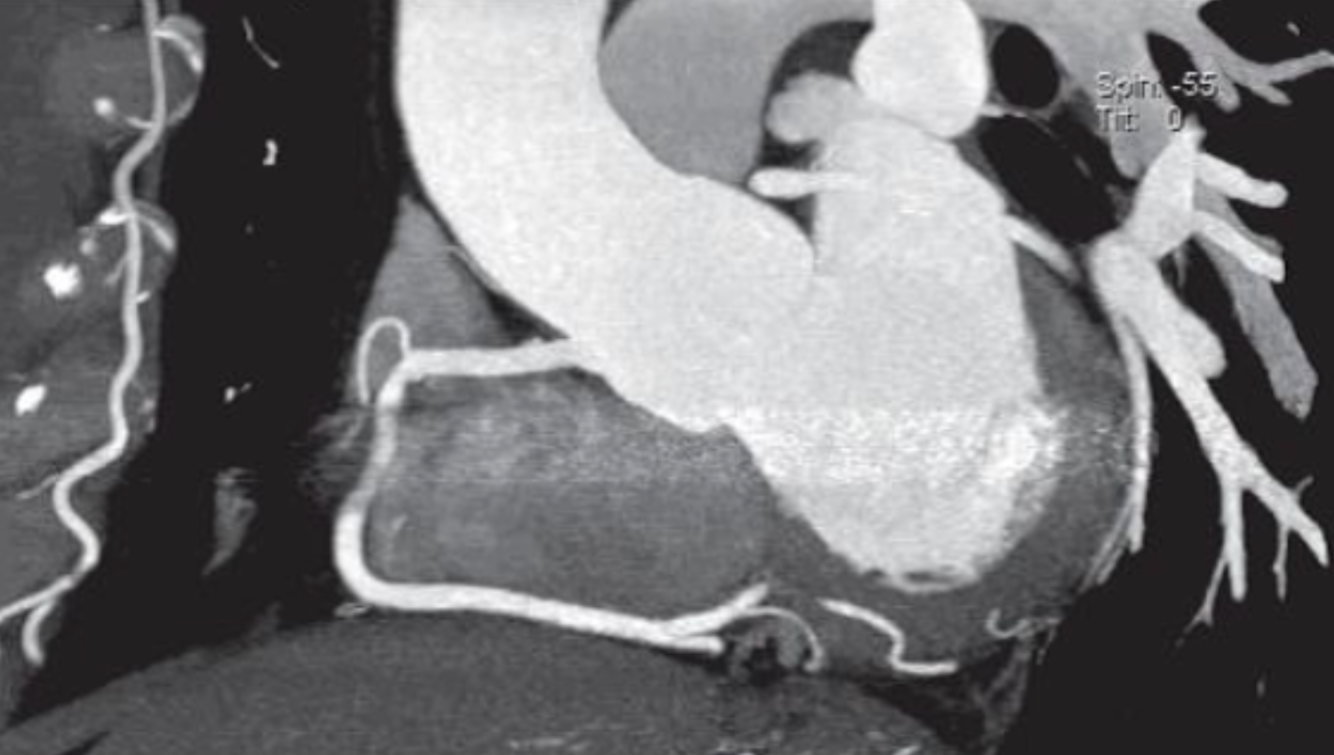

Describe the CT scan protocol/view:

Oblique MIP of the RCA

Describe the RCA findings in this image:

Cardiac Motion Artifact